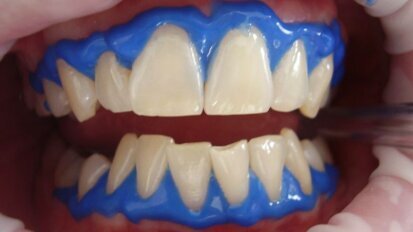

Vereenvoudigd universeel composiet voor esthetisch herstel van een zwaar gerestaureerd bovenfront

Wat zijn de esthetische resultaten van het gebruik van 3M™ Filtek™ Universal Restorative in een zwaar gerestaureerd bovenfront? In deze klinische casus ...